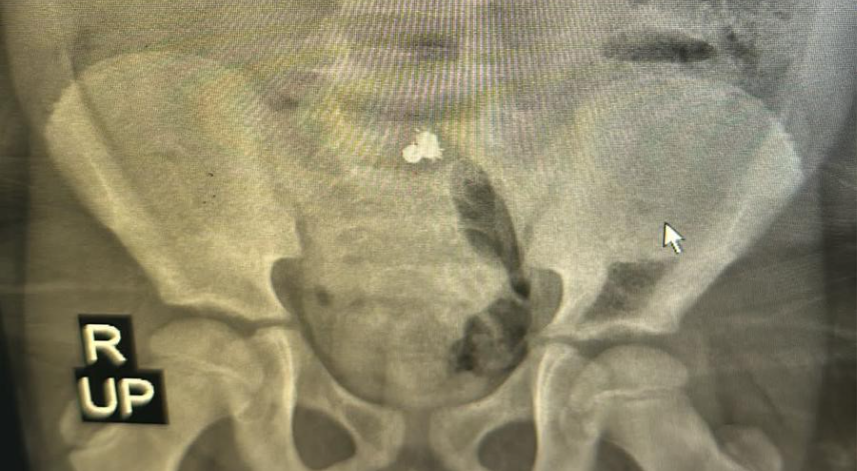

Çekilen röntgende bağırsağına yapışmış 3 parça mıknatıs tespit edilen çocuğun ameliyatına karar verildi.

Cerrahi Tıp Bilimleri Bölümü Çocuk Cerrahisi Anabilim Dalı Dr. Öğr. Üyesi Halil İbrahim Çakmak ve ekibi tarafından gerçekleştirilen operasyonla mıknatıslar çıkarılarak Miraç'ın üç yerden delinen bağırsağı dikildi.